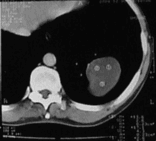

Эхинококкоз легких